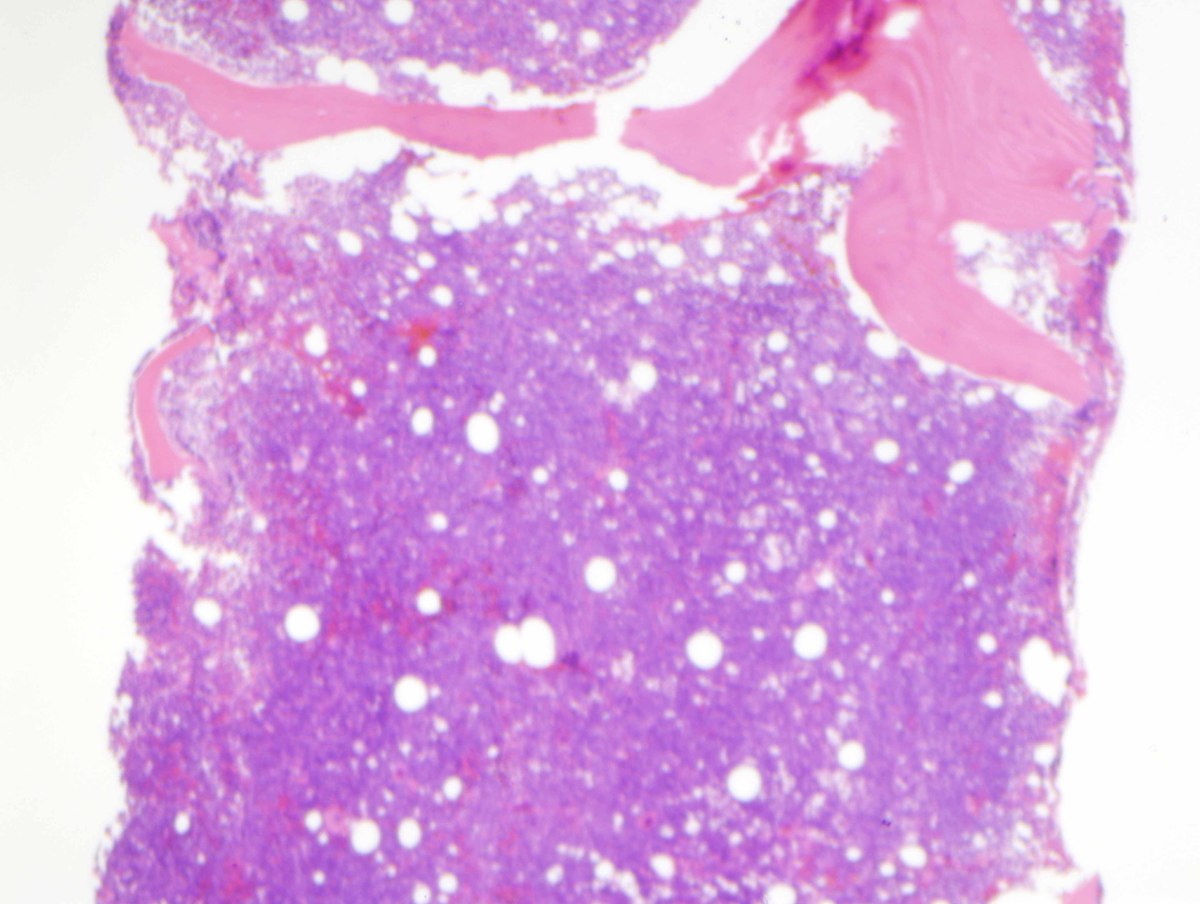

| C. Bone marrow core biopsy which is hypercellular and subtotally replaced by sheets of blasts (H&E, 40x). | ![]() |

The aspirate biopsy shows increased blasts as the predominant cell type (85%), with high nuclear:cytoplasmic ratios, several small nucleoli, and agranular cytoplasm. No Auer rods are seen. Cytochemical stains for myeloperoxidase and non-specific esterase (alpha naphthyl butyrate) show that the blasts are negative for myeloperoxidase and show focal dot-like positivity for non-specific esterase (NSE). Similar results are obtained with repeat of NSE cytochemistry on peripheral blood.The core biopsy is hypercellular (95%) with sheets of large, atypical mononuclear cells that virtually replace the normal bone marrow elements. Mitotic figures are frequent.IMMUNOHISTOCHEMISTRY AND FLOW CYTOMETRY